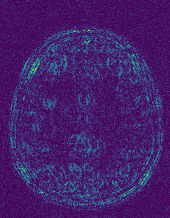

6.2.2 Quality of the Predicted Edges

EPN is utilized to provide edge priors for later reconstruction, so the quality of the predicted edges is very important. In Fig. 10, we provide some qualitative results of the predicted edges of EPN on three multi-coil datasets. Among them, the GT edges are extracted using the Sobel operator. As can be seen from the images, our proposed EPN can predict an approximate contour for the overall subject and can reconstruct accurate edges close to the GT edges under two acceleration factors. This fully verifies the effectiveness and excellence of the proposed EPN.

(a)

(b)

(c)

(d)